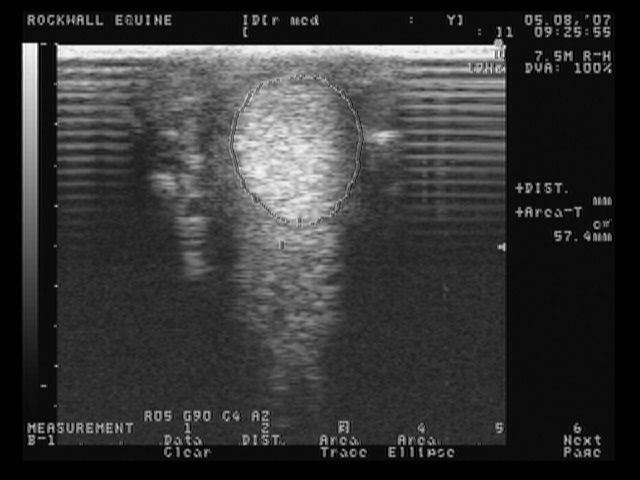

right medial front

These are the most recent ultrasound images of my horses legs, done about 2 weeks ago. The original injury was in January, so he is about 4 months into healing. The left lateral is normal.